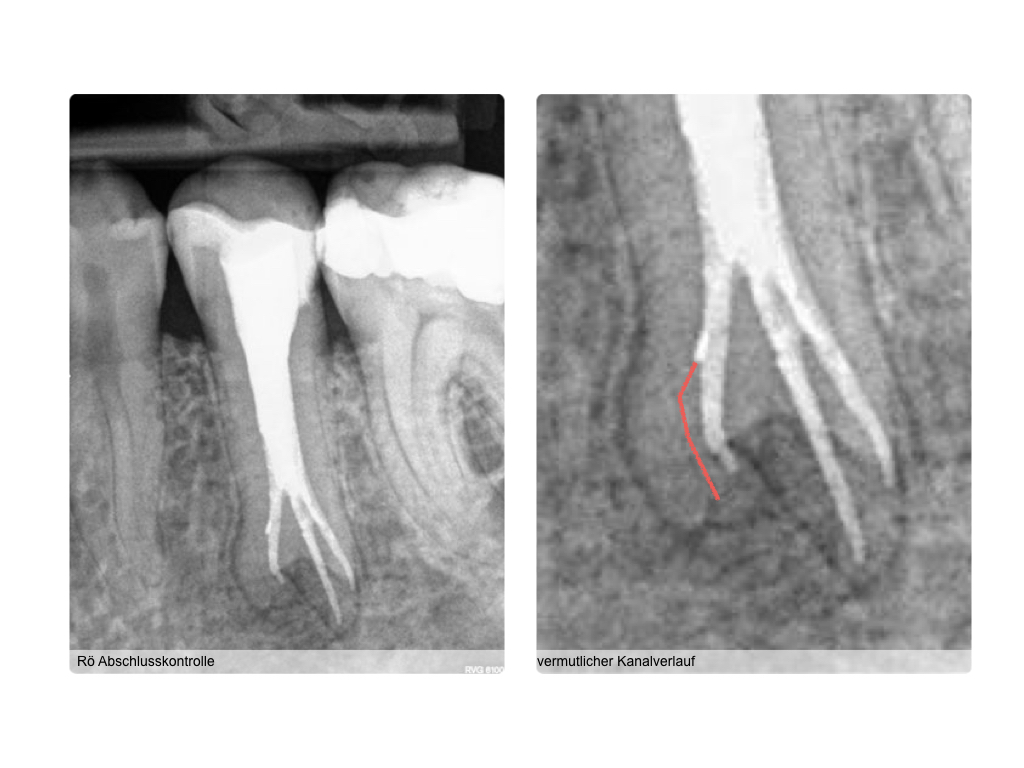

WS_Fallvorstellung15_12_2.008 Veröffentlicht 6. Dezember 2015 am 1024 × 768 in 2015 Fallvorstellung 1